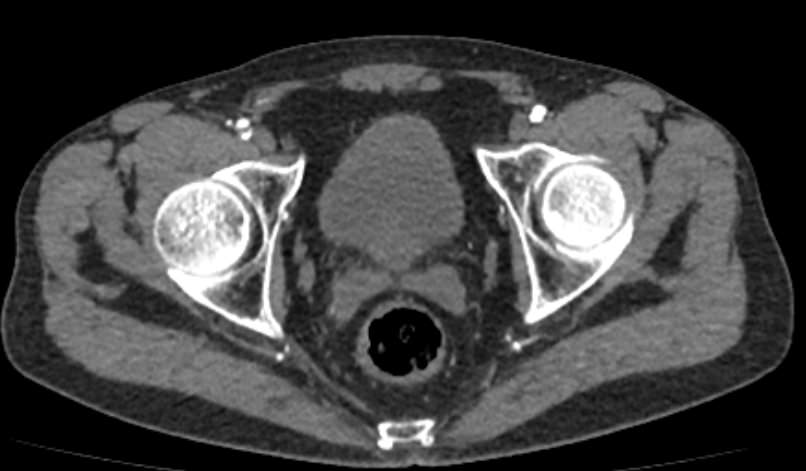

Основные показания для проведения КТ брюшного отдела аорты и артерий нижних конечностей могут включать:

• Аневризмы: оценка и диагностика аневризм брюшной аорты.

• Стенозы и окклюзии: выявление и оценка степени сужения или блокировки артерий.

• Тромбозы: обнаружение тромбов и оценка их размера и локализации.

• Атеросклероз: определение степени и распространенности атеросклеротических изменений.

• Подготовка к хирургическим вмешательствам: планирование сосудистых операций и вмешательств.

• Оценка послеоперационного состояния: контроль за состоянием сосудов после хирургических вмешательств.